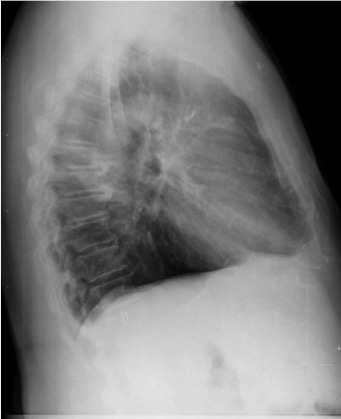

CASO: Febrícula y tos de 4 días de evolución.

Hallazgos:

- En la placa PA se observa una asimetría en los hilios pulmonares, el hilio izquierdo tiene una densidad aumentada.

- Tras examinar la placa lateral se observa un aumento de densidad en la columna que puede ser compatible con una condensación, es el signo de la desnificación vertebral.

SIGNO DE LA DENSIFICACIÓN VERTEBRAL: En la radiografía lateral normal, la densidad de la columna torácica tiende a disminuir desde la parte superior hasta el diafragma; la alteración de ese patrón por la presencia de una densidad superpuesta a la columna, indica la existencia de una consolidación pulmonar. Este signo adquiere especial valor cuando en la proyección posteroanterior la consolidación está oculta en el espacio retrocardíaco o en la base pulmonar.